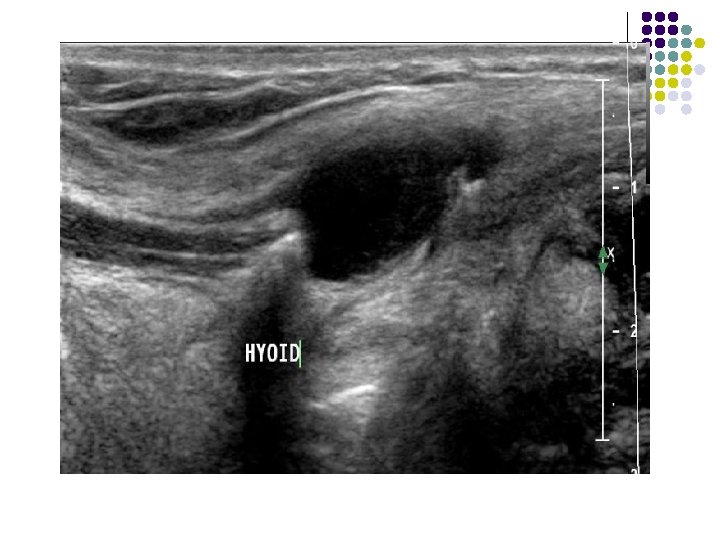

CASE 2 l A 17 YEARS OLD FEMALE PRESENTED WITH PAINLESS ANTERIOR MIDLINE NECK MASS. O/E: l Swelling moves on deglutition and on protrusion of tongue.

FINDINGS: sagittal ultrasound image (left is superior) shows a cystic anechoic structure just below the level of the hyoid bone. A small beak of the cyst can be seen passing superiorly over the hyoid.

l Thyroglossal duct cysts develop anywhere along the course of the duct remnant, from the base of the tongue to the suprasternal region. l Frequently located in the region of the hyoid bone. l Cysts located above the level of the thyroid cartilage are usually midline, while cysts located below the level of the thyroid cartilage are off midline. l Presents as an asymptomatic, mobile mass in the anterior triangle of the neck WHICH MOVES ON DEGLUTITION AND ON PROTRUSION OF TONGUE. l Patients present in their teens or twenties because of enlargement and/or infection.

IMAGING FEATURES: l On ultrasound, they appear as hypoechoic masses with few septae and internal echoes. l CT scan : They are hypodense and well defined with minimal enhancement of the margins on contrast scans. l MR can also be used for superior soft tissue evaluation. The lesions are hypointense on T 1 W images and hyperintense on T 2 W images. l l These lesions usually lie medial to the sternocleidomastoid muscle, anterior to the carotid sheath and lateral to the thyroid gland.

IN OUR PATIENT… l l Midline ant. Neck mass which moves on protrusion of toungue. Anechoic cystic lesion in infrahyoid region with beak extenmding in suprahyoid region on usg. on. Ct. . Low density lesion with mininmal rim enhancement and in classical location. DIAGNOSIS: THYROGLOSSAL CYST